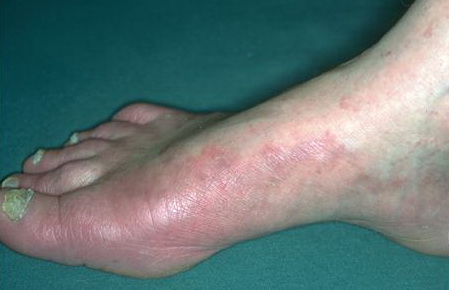

Vesiculo-Bullous Type.

The vesiculo-bullous type of tinea pedis, typically caused by T. mentagrophytes, features tense vesicles larger than 3 mm in diameter, vesiculopustules, or bullae on the thin skin of the sole and periplantar areas . It is rarely reported in childhood, but the most common etiologic agent in childhood is T. rubrum.